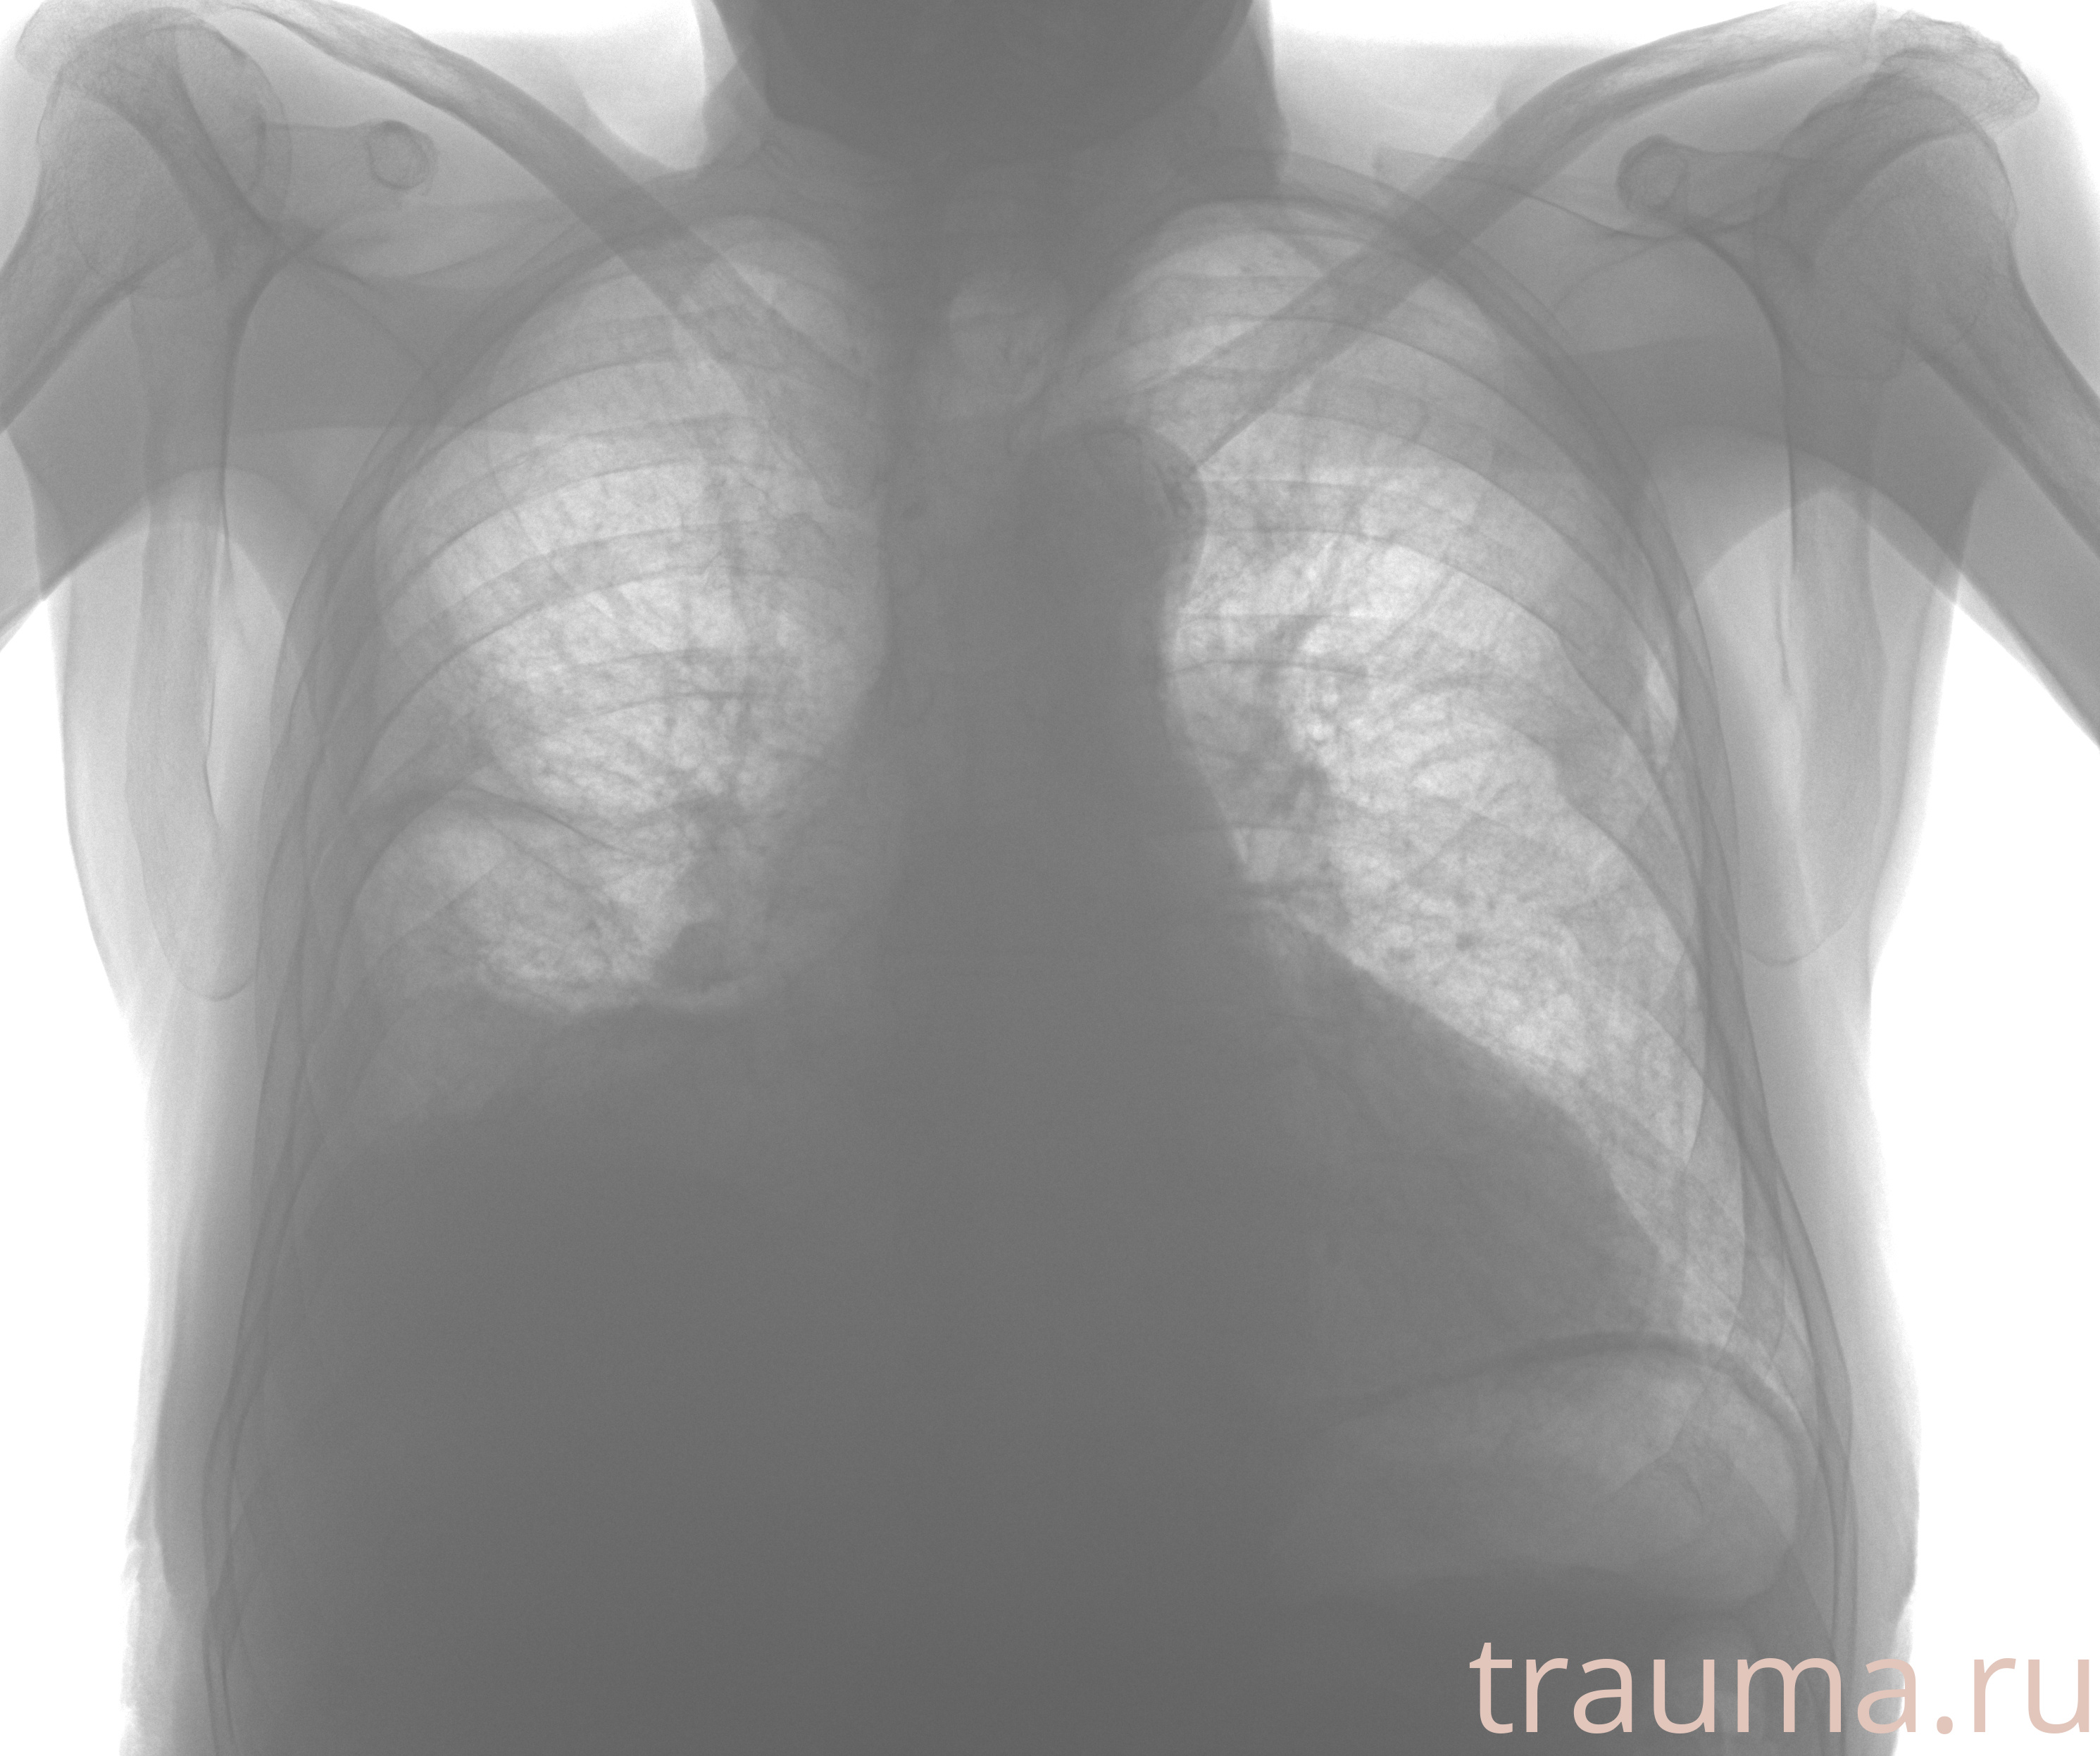

Рентгенограммы

Рентген на дому: по вашему адресу приезжает врач-рентгенолог, травматолог-ортопед с мобильным рентгеновским аппаратом, проводит диагностику травмы или заболевания, делает необходимые рентгенограммы, дает рекомендации по дальнейшему лечению. Получить качественные снимки в домашних условиях возможно благодаря уникальной методике, разработанной МосРентген Центром для института  Склифосовского

при переломе шейки бедра и пневмонии от компании МосРентген Центр - партнера Института имени Склифосовского